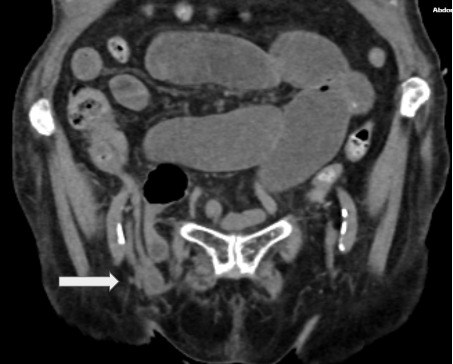

A 93-year-old woman presented to the emergency department with a 1-day history of right lower quadrant abdominal pain that moved into the right groin area. On physical examination, presented with left lower quadrant pain, decreased peristaltic sounds and abdominal distension. Laboratory data demonstrated leukocytosis. Abdominal computed tomography showed an incarcerated right femoral hernia of the appendix with dilatation of the appendix (Figure 1 & 2). She underwent laparoscopic surgery where an incarcerated colon was observed in the internal ring of the right femoral canal (Figure 3 & 4). Appendectomy was performed after reduction (Figure 5). The right femoral hernia of the internal ring was closed with a primary suture (Figure 6 & 7). Pathologic anatomy revealed appendicitis with reactive lymphoid aggregates. From the beginning he was treated with antibiotics, and adequate parenteral fluid management. The postoperative period was adequate, she did not present abdominal symptoms such as pain or nausea. She was discharged 4 days after a successful appendectomy and hernia repair.

Figure 1 Tomography of the abdomen in coronal section , distended bowel loops secondary to right femoral hernia.